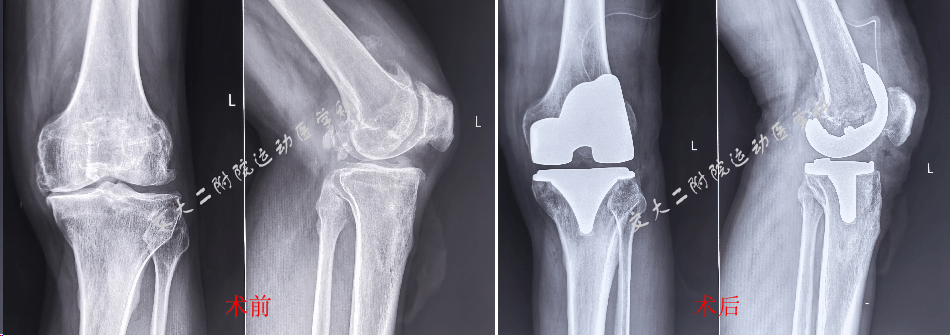

手术前后膝关节X线片

此次膝关节置换手术的顺利开展,是医院综合实力的又一次有力彰显。合并HIV的膝关节置换手术,因其特殊的病理生理状态,手术风险和难度呈几何倍数增长。不仅要考虑膝关节置换手术本身的复杂性,如关节假体的精准植入、周围软组织的妥善处理 ,还要兼顾HIV患者免疫力低下易感染、身体机能恢复慢等问题。然而,时志斌主任带领的运动医学科团队凭借丰富的临床经验、精湛的专业技术以及对前沿医学的深入研究,在术前进行了全面而细致的评估,制定出科学、精准的手术方案,从每一个细微环节入手,确保手术的安全性与有效性。